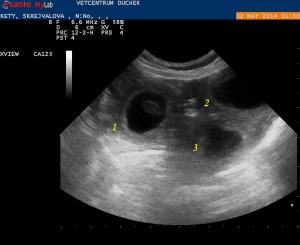

27.4. Konečně to všechno víme - Kety čeká 4 štěňátka, nahmatala jsem si je a taky našla na ultrazvuku. Pro neznalé jsem balonky očíslovala